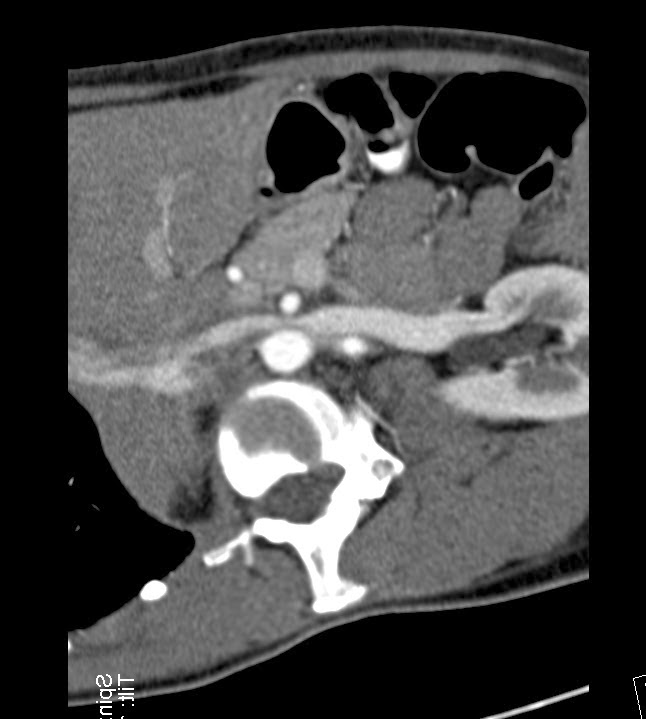

| Left renal vein (left parasagittal reconstruction) |

| Note the minimal dorsal deviation of the descending aorta at the level of the compressed left renal vein. |

Compression of the left renal vein by the superior mesenteric artery and aorta.